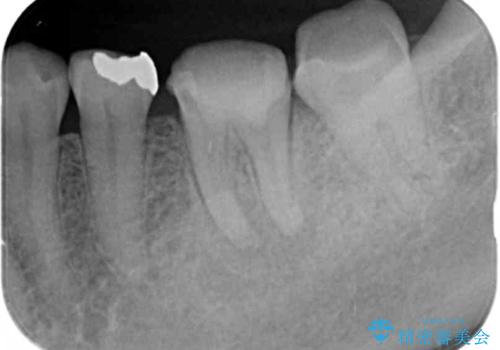

X線写真より根の先に病変が認められたため、根管治療を行ったのちジルコニアクラウンによる咬合機能回復治療を計画します。